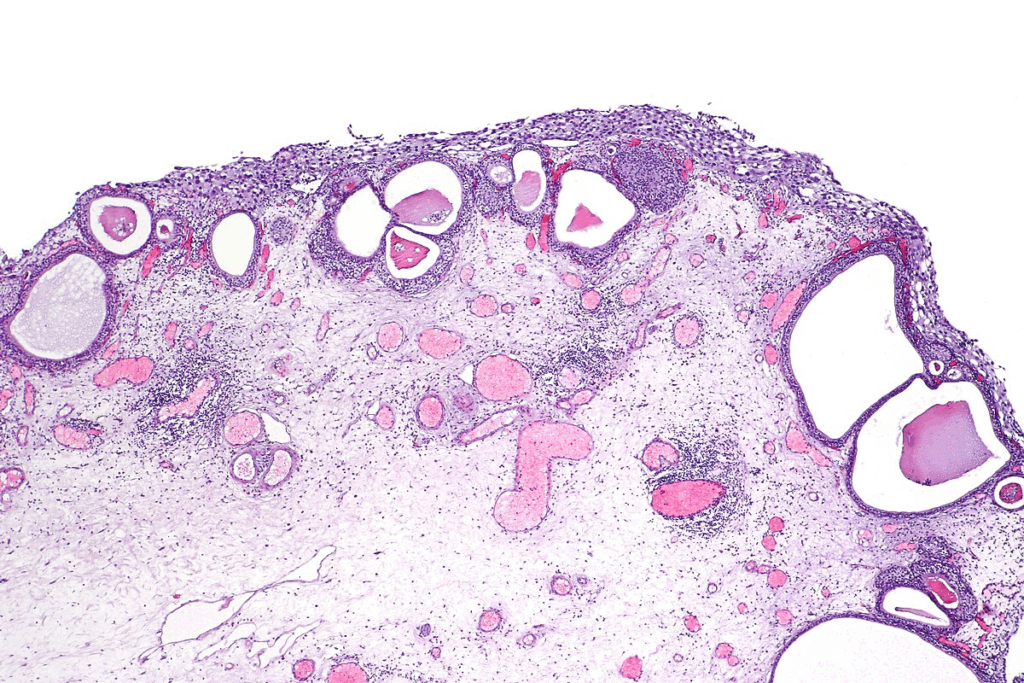

CIS has severely dysplastic urothelial cells that haven’t invaded the bladder wall. These cells show nuclear atypia, like big nuclei and irregular shapes. CIS cells are often disorganized and lose normal cell structure.

Nuclear atypia in CIS shows its cancer risk. Cells in CIS have dark nuclei due to more DNA. They also vary in size and shape, showing they are cancerous.

CIS cells also change in cytoplasm, like density and structure. These changes help doctors diagnose CIS and tell it apart from less serious urothelial lesions.

CIS is different from other bladder cancers, like low-grade papillary urothelial carcinoma. CIS is flat and non-papillary, making it hard to spot during cystoscopy. Unlike papillary tumors, CIS doesn’t grow in a papillary shape.